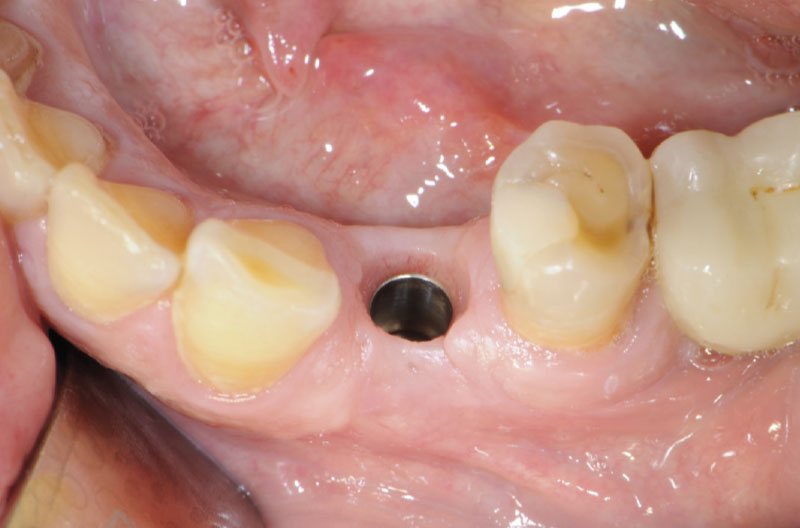

Fig. 7 – Tappo di guarigione in situ

Fig. 8 – Situazione dopo aver tolto il tappo di guarigione

Fig. 9 – Inserimento del manufatto protesico

Fig. 10 – Manufatto protesico in situ dopo averlo inconato con il percussore con punta in PEEK